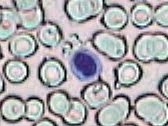

Práctica de Frotis sanguíneo 29